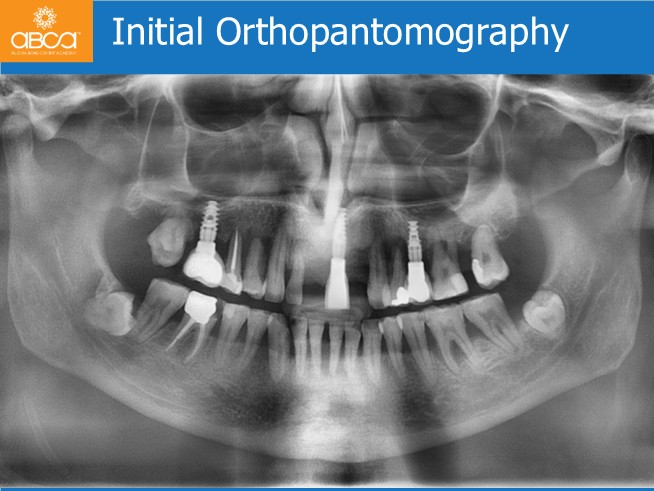

The patient is a 62-year-old man, with type I diabetes. He presents with complaints of difficulty in chewing and a lack of aesthetic and mobility in the remaining maxillary teeth. The oral exam shows a lack of teeth #14 (5) – #11 (8) and #22 (10). The patient had already 3 individual implants placed #16 (3),#21 (9) and #25 (13). Most of the remaining natural teeth were in bad condition with mobility due to the marked periodontal bone loss. The complementary exams confirmed the visual examination, and the virtual planning confirms the possible use of the old implants combined in new rehabilitation. The patient wants a fixed rehabilitation.